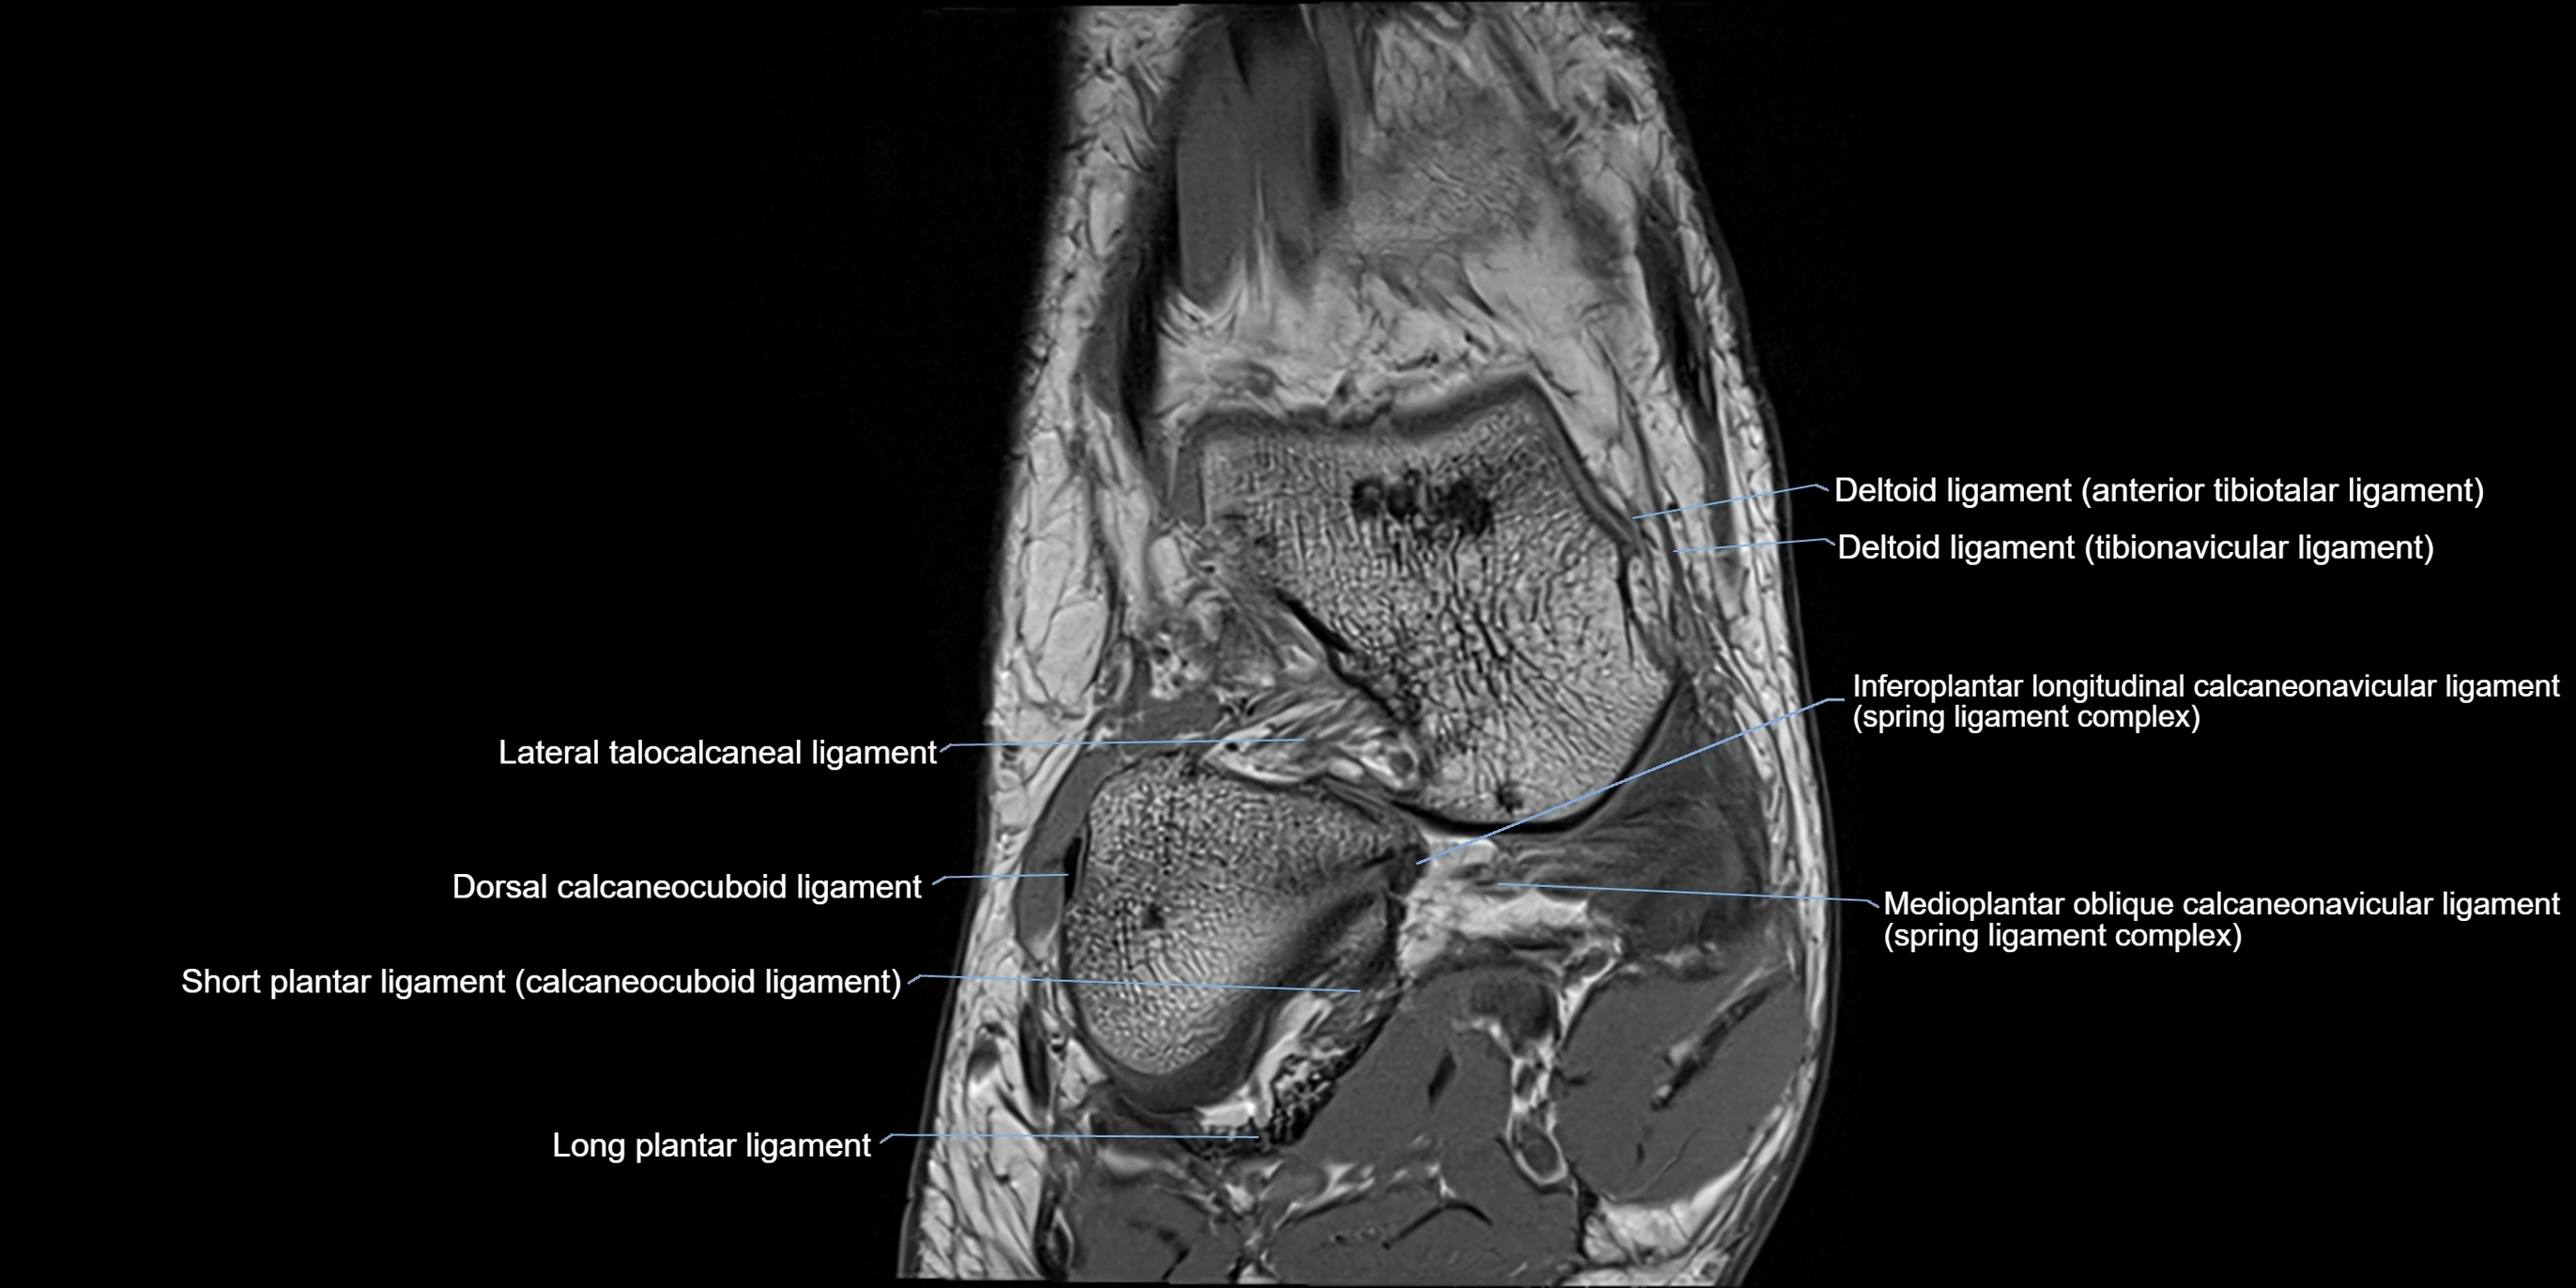

MRI image

image